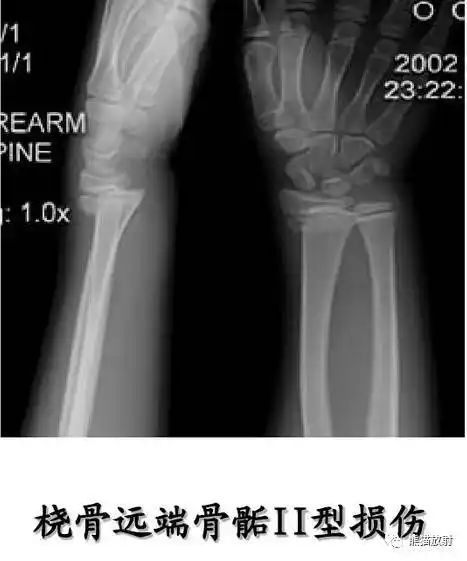

桡骨远端干骺骨折手法复位一例